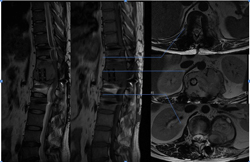

图3-1,CT矢状面和冠状面重建,显示病变为成骨性,病变内有点状钙化。

图3-2,CT横断面显示病变累及L2-L3水平椎骨。

图3-3,MRI矢状面及冠状面显示病变侵入椎管明显压迫硬膜囊和马尾神经

图3-4,MRI横断面显示病变存在软组织成分,在左侧L2-3椎间孔区肿瘤累及椎管内外,明显压迫马尾神经,并且包绕左侧L2神经根。